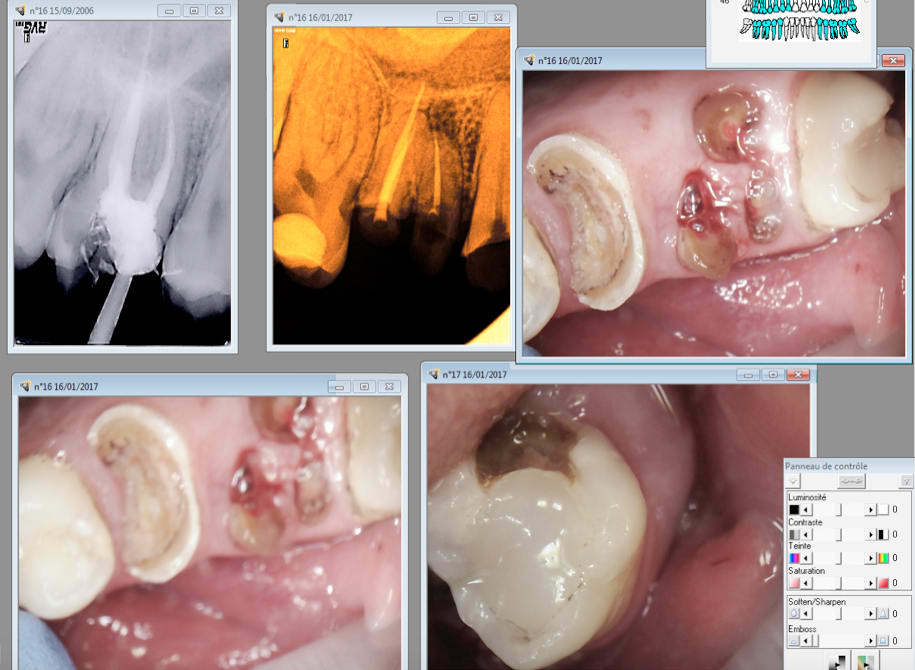

Tiens casa quand tu soignes la dent causale tu ne les revois plus........ non plus.

Enfin des fois si. 2006........2017. Et pas pour une visite de controle. -) -)

Je pense qu'il y a une image apicale sur 16 car je n'avais pas traité le MV2 à l'époque. Heureusement que je n'ai pas fait de couronne hein ? -) -))))

C'est la 15 qui a motivé la consult. Bizarre. -))))

Je vais commencer par 27....... une fois le devis signé ! -)))))))

Ah oui radios 8 secteurs. -))))

AH ! oui il a tardé en plus ( endo en avril 2016) ca n'arrange pas les choses-)))

Houlà , faut que je réponde là !! alors oui enlaye , tout est naturel chez moi ! pas une couronne, seulement une 15 dévitalisée (erreur de jeunesse à la fac)et non couronnée depuis 10 ans facile (tu vois chicot ça peut se faire si on a une bonne occlusion , une bonne hygiène et je ne suis pas une forcenée de la brosse à dent ! ) ce qui m'amène à ton cas : tu lui a fais quoi sur cette 16 à part l'endo il y a 11 ans ? rien peut-être et regarde la 15 en 11 ans complètement rongée .... donc le mec il a un fort pouvoir carieux et c'est avec des gars comme ça qu'on peut se prendre pour le (la) pire des nazes ! même couronnée , elle serait partie en sucette cette dent ... (il me semble que tu as un exemple proche ...) donc ton exemple ne démontre rien . Quant à ton 2 ème cas , comme Enlaye , SC33 , , ça vaut le coup , sinon t'es sur d'avoir de gros pb paro assez rapidement ...

Si un cavit. Et un devis pour une couronne. Mais après l'endo. Erreur fatale. -)

ah ben ça fait 6 mois qu'elle baigne dans la salive en gros cette 36 .. du coup la digue et tout le tintouin ben ça sert plus à grand chose , elle avait un cavit celle là aussi ...ça fait 2 patients ( voire 3 avec l'urgence qui est parti ailleurs ) qui n'ont pas poursuivi leur soin d'après les exemples récents que tu nous donnes à voir ... attention chicot faut fidéliser un peu quand même sinon tu vas mettre la clé sous la porte !!! et comme visiblement tu n'en prends pas beaucoup vu ton organisation , va falloir un peu plus expliquer ce que tu fais au patient (pas seulement à nous!! ) sinon ils sont plutôt enclin à se tirer visiblement ...